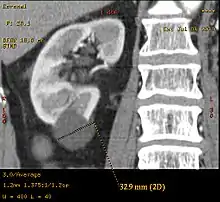

| Renal cyst | |

![]() | |

| Renal cyst of the left kidney (hyperintense area) as shown on MRI. | |